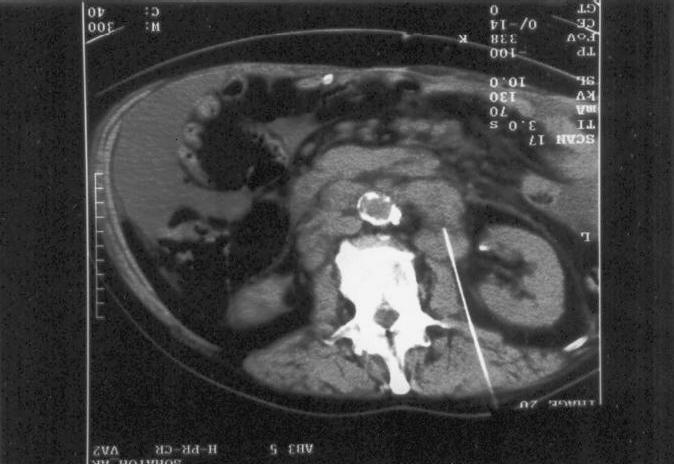

Mr. Schwarz was a 63 year old alcoholic. Eleven years before, his wife had left him because of his alcohol use and related behavior. According to her, he had kept her at a distance during all of their marriage. They never officially divorced, and they still met occasionally. When she did leave him, she promised that if he ever would really need her, she would be there for him. The patient got ill and multiple sites of abnormal tissue were found in the belly. The scan shows some of it around the abdominal aorta.

A biopsy-needle (on the CT scan  coming in from below) was used to collect some tissue for pathological analysis. This showed poorly differentiated adenocarcinoma.